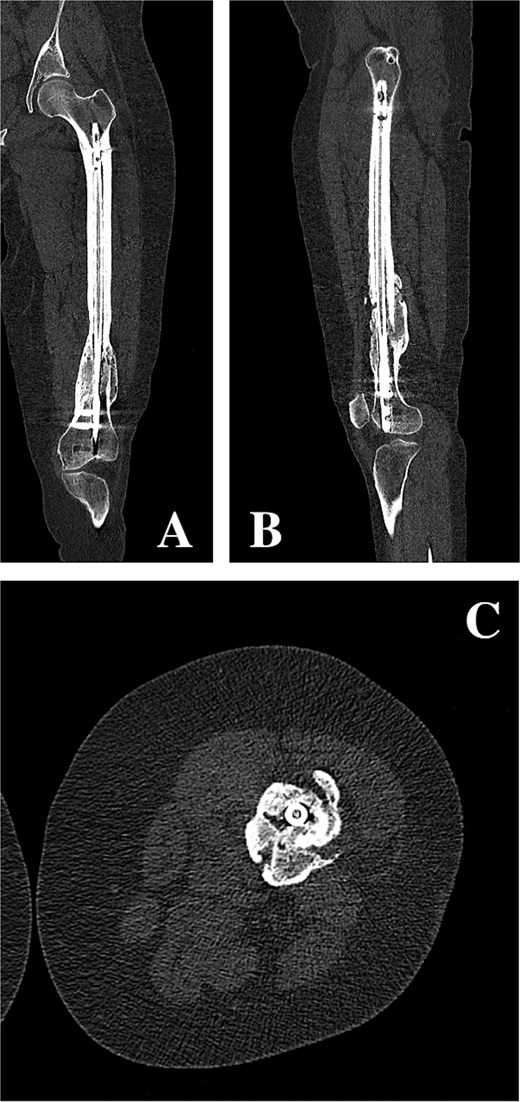

On clinical examination, the left thigh was swollen and ecchymotic with visible deformity. Passive and active range of motion at the hip and knee was markedly restricted due to pain. Distal neurovascular function was intact. All laboratory investigations were negative or normal. Radiographs of the femur, hip, and knee revealed a hypertrophic malunion at the distal femur with a proximal periprosthetic fracture and an intramedullary nail inserted (Fig. 1). A preoperative non-contrast computerized tomography (CT) scan of the left thigh confirmed an old distal femoral fracture with in situ fixation and extensive hypertrophic callus. Multiple small free bone fragments were seen in the distal thigh. The hardware extended beyond the distal and medial cortical margins, with screws also breaching the cortex. An oblique fracture line was noted proximally adjacent to the proximal screw, without displacement. No soft tissue hematoma or joint effusions were identified (Fig. 2). The patient was admitted for surgical management. Revision antegrade nailing was performed intraoperatively. Upon removal of the retrograde nail it was confirmed to be an antegrade construct (Fig. 3). A correctly sized antegrade femoral nail was inserted via the proximal entry point under fluoroscopic guidance. Postoperative imaging demonstrated satisfactory alignment and stable fixation. At follow-up, the patient reported improved mobility and reduced pain. Radiographs showed signs of progressive healing. No signs of infection, implant loosening, or neurovascular compromise were observed (Fig. 4).

(A, B) Coronal and sagittal CT reconstructions of the left femur demonstrating an intramedullary femoral nail with extensive hypertrophic callus formation at the site of a chronic distal femoral malunion, along with an oblique proximal periprosthetic fracture adjacent to the proximal locking screw. (C) Axial CT image demonstrating hypertrophic callus consistent with a distal femoral malunion surrounding an intramedullary femoral nail.